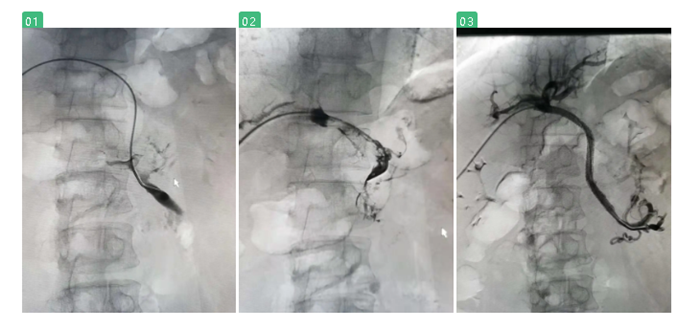

在陸煒的指導(dǎo)下,血管外科診療組長程國兵副主任醫(yī)師為江先生施行“經(jīng)皮肝穿刺門靜脈、腸系膜上靜脈造影+Angiojet吸栓+支架植入球囊擴(kuò)張術(shù)”。

經(jīng)過季肋部穿刺至門靜脈時(shí),發(fā)現(xiàn)江先生的門靜脈及腸系膜上靜脈已完全閉塞,程國兵巧妙地引入導(dǎo)絲、放入導(dǎo)管,一點(diǎn)點(diǎn)清除門靜脈血栓,最后,成功放入支架。

術(shù)中復(fù)查造影,顯示支架定位準(zhǔn)確,展開良好,腸系膜上靜脈及門靜脈主干血流通暢。

圖一、二:血管閉塞,充滿血栓 圖三:血栓清除,恢復(fù)血流